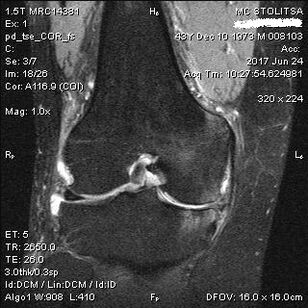

The diagnosis of osteoarthritis of the knee joint takes place in the office of a rheumatologist or orthopedist.The doctor examines the affected joint, palpates it, listens to complaints and asks additional questions.Performs several tests - for example, asking the patient to bend the leg or take a few steps.Then, if it is necessary to specify the stage of the disease or the nature of the pathological changes, he will direct you towards additional studies.For example, for CT scanning or x-ray.